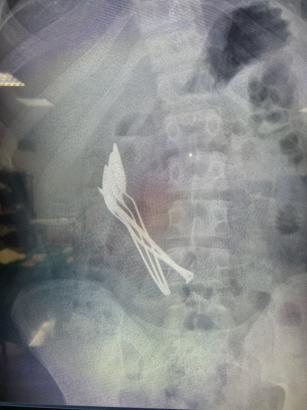

15 yaşındaki çocuğun midesinden 4 kaşık ve 1 çivi çıkarıldı

Furkan KAVUKLU/KAYSERİ, (DHA)- KAYSERİ'de 15 yaşındaki erkek çocuğunun midesinden, 2 saat süren operasyonla 4 metal tatlı kaşığı ve 1 çivi çıkarıldı.

Kentte, bir aile çocuklarının mide şikayeti üzerine hastaneye başvurdu. Kayseri Şehir Hastanesi’nde yapılan incelemede çocuğun midesinde 4 metal tatlı kaşığı ve 1 çivi görüldü. Kayseri Şehir Hastanesi Çocuk Cerrahisi ve Ürolojisi Anabilim Dalı Başkanı Doç. Dr. Mustafa Erman Dörterler ve ekibi tarafından yaklaşık 2 saat süren operasyonda çocuğun midesindeki kaşıklar ve çivi çıkarıldı. Erkek çocuğu tedavisinin ardından taburcu edildi. (DHA)